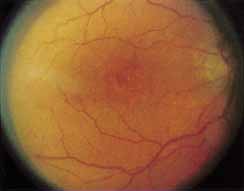

Although there is no reported genetic heterogeneity, there is wide phenotypic variation within the disorder. The major finding within the macula is a classic radial cystic maculopathy. Although retinal signs have been described in infants as young as 3 months, foveal schisis may be difficult to detect, leading to underdiagnosis. The diagnosis is usually not made until the affected male reaches school age (4 to 8 years of age) and encounters visual problems secondary to foveal involvement. Typical foveal schisis findings have been reported in 68% to 100% of eyes within various series.37,38 Foveal schisis is the only finding in about half the cases. It is characterized by the presence of radiate perifoveal microcysts located in the nerve fiber layer (Fig. 1) with radiate plications of the overlying internal limiting membrane that are seen especially well on monochromatic (red-free) photography (Fig. 2). The microcystoid change may slowly progress to form a macular cyst or hole. Foveal schisis has been reported in association with Goldmann-Favre vitreotapetoretinal dystrophy and rarely may be seen in rod-cone dystrophy or as an autosomal dominant or recessive condition.39–43